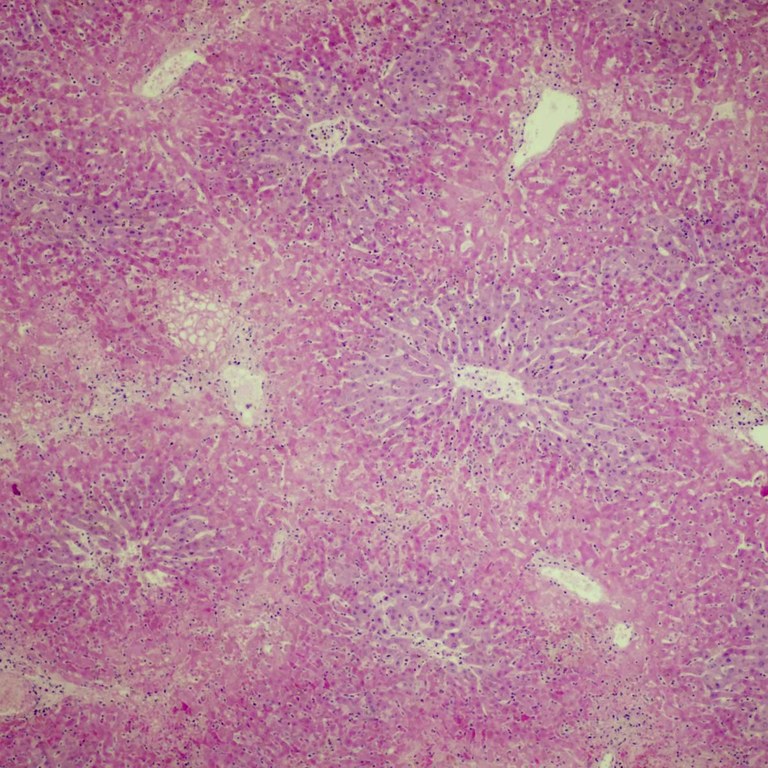

Hepatocellular necrosis due to RHDV2

In this view, several complete lobules can be seen and there is marked acute hepatocellular necrosis (pinker colour) with only the hepatocytes (bluer colour) close to the central vein (whitish 'hole') being spared. This picture is typical of RHD. RHDV2 was confirmed by PCR testing in this case.